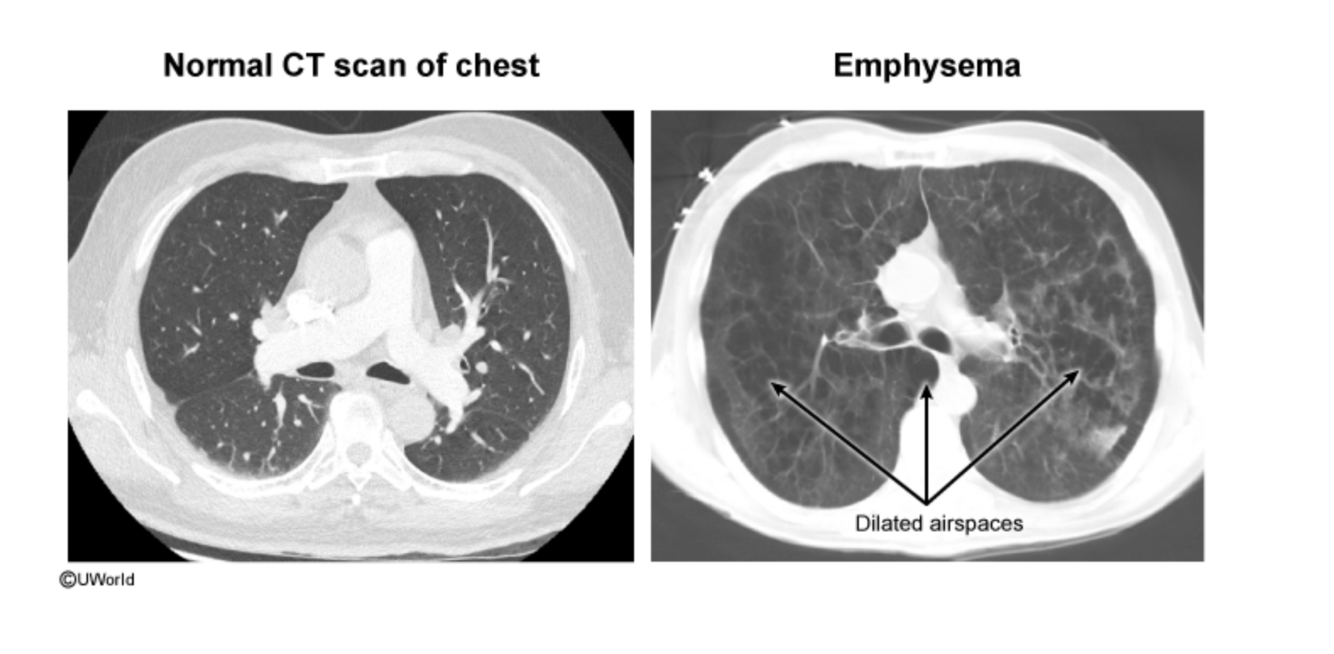

What imaging findings are seen in COPD on chest X-ray or CT scan?

Hyperinflation, increased lung translucency, flattened diaphragm, and subpleural blebs.

What are the classic physical exam findings for emphysema?

Decreased breath sounds, hyperinflation, barrel chest, pursed lip breathing (‘pink puffers’).

What is the key pathophysiologic process in emphysema?

Destruction of alveolar walls due to excess protease activity, leading to air trapping and loss of elastic recoil.